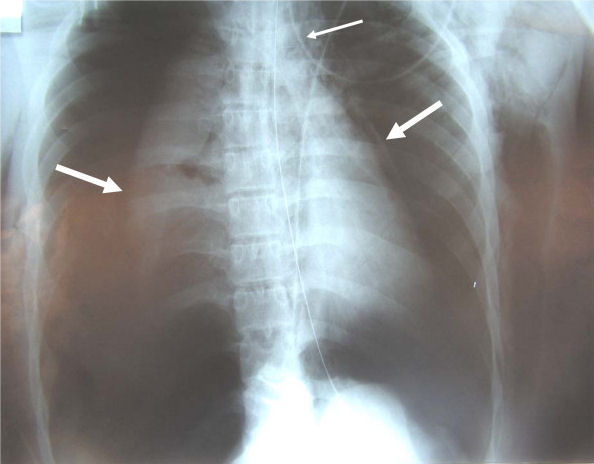

Bilateral pneumothorax

Source: Le Guen et al. Critical Care 2007 11:R94 doi:10.1186/cc6109 Date: 3 September 2007 Author: Morgan Le Guen, Catherine Beigelman, Belaid Bouhemad, Yang Wenjïe, Frederic Marmion Licence: